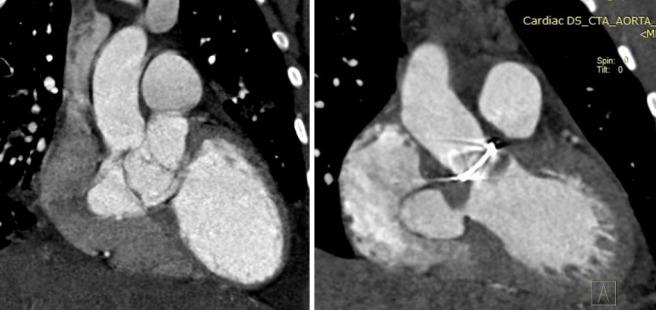

Aneurysm of the right sinus of Valsalva and the membranous septum: Haemodynamic and clinical characterization.

https://cdn.ncbi.nlm.nih.gov/pmc/blobs/bc8f/4104383/1617318f1f99/gcsp-2014-090-g001.jpg